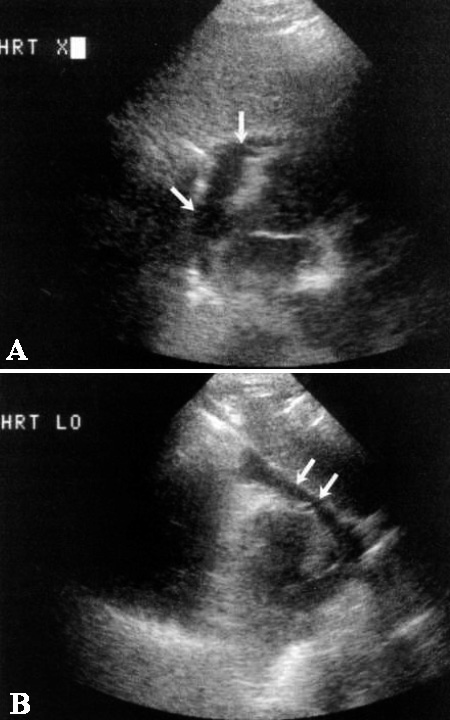

Фото 2. Перикардиальная жидкость. А – поперечное изображение и В – продольное изображение сердца из подмечевидного доступа: стрелками обозначена жидкость